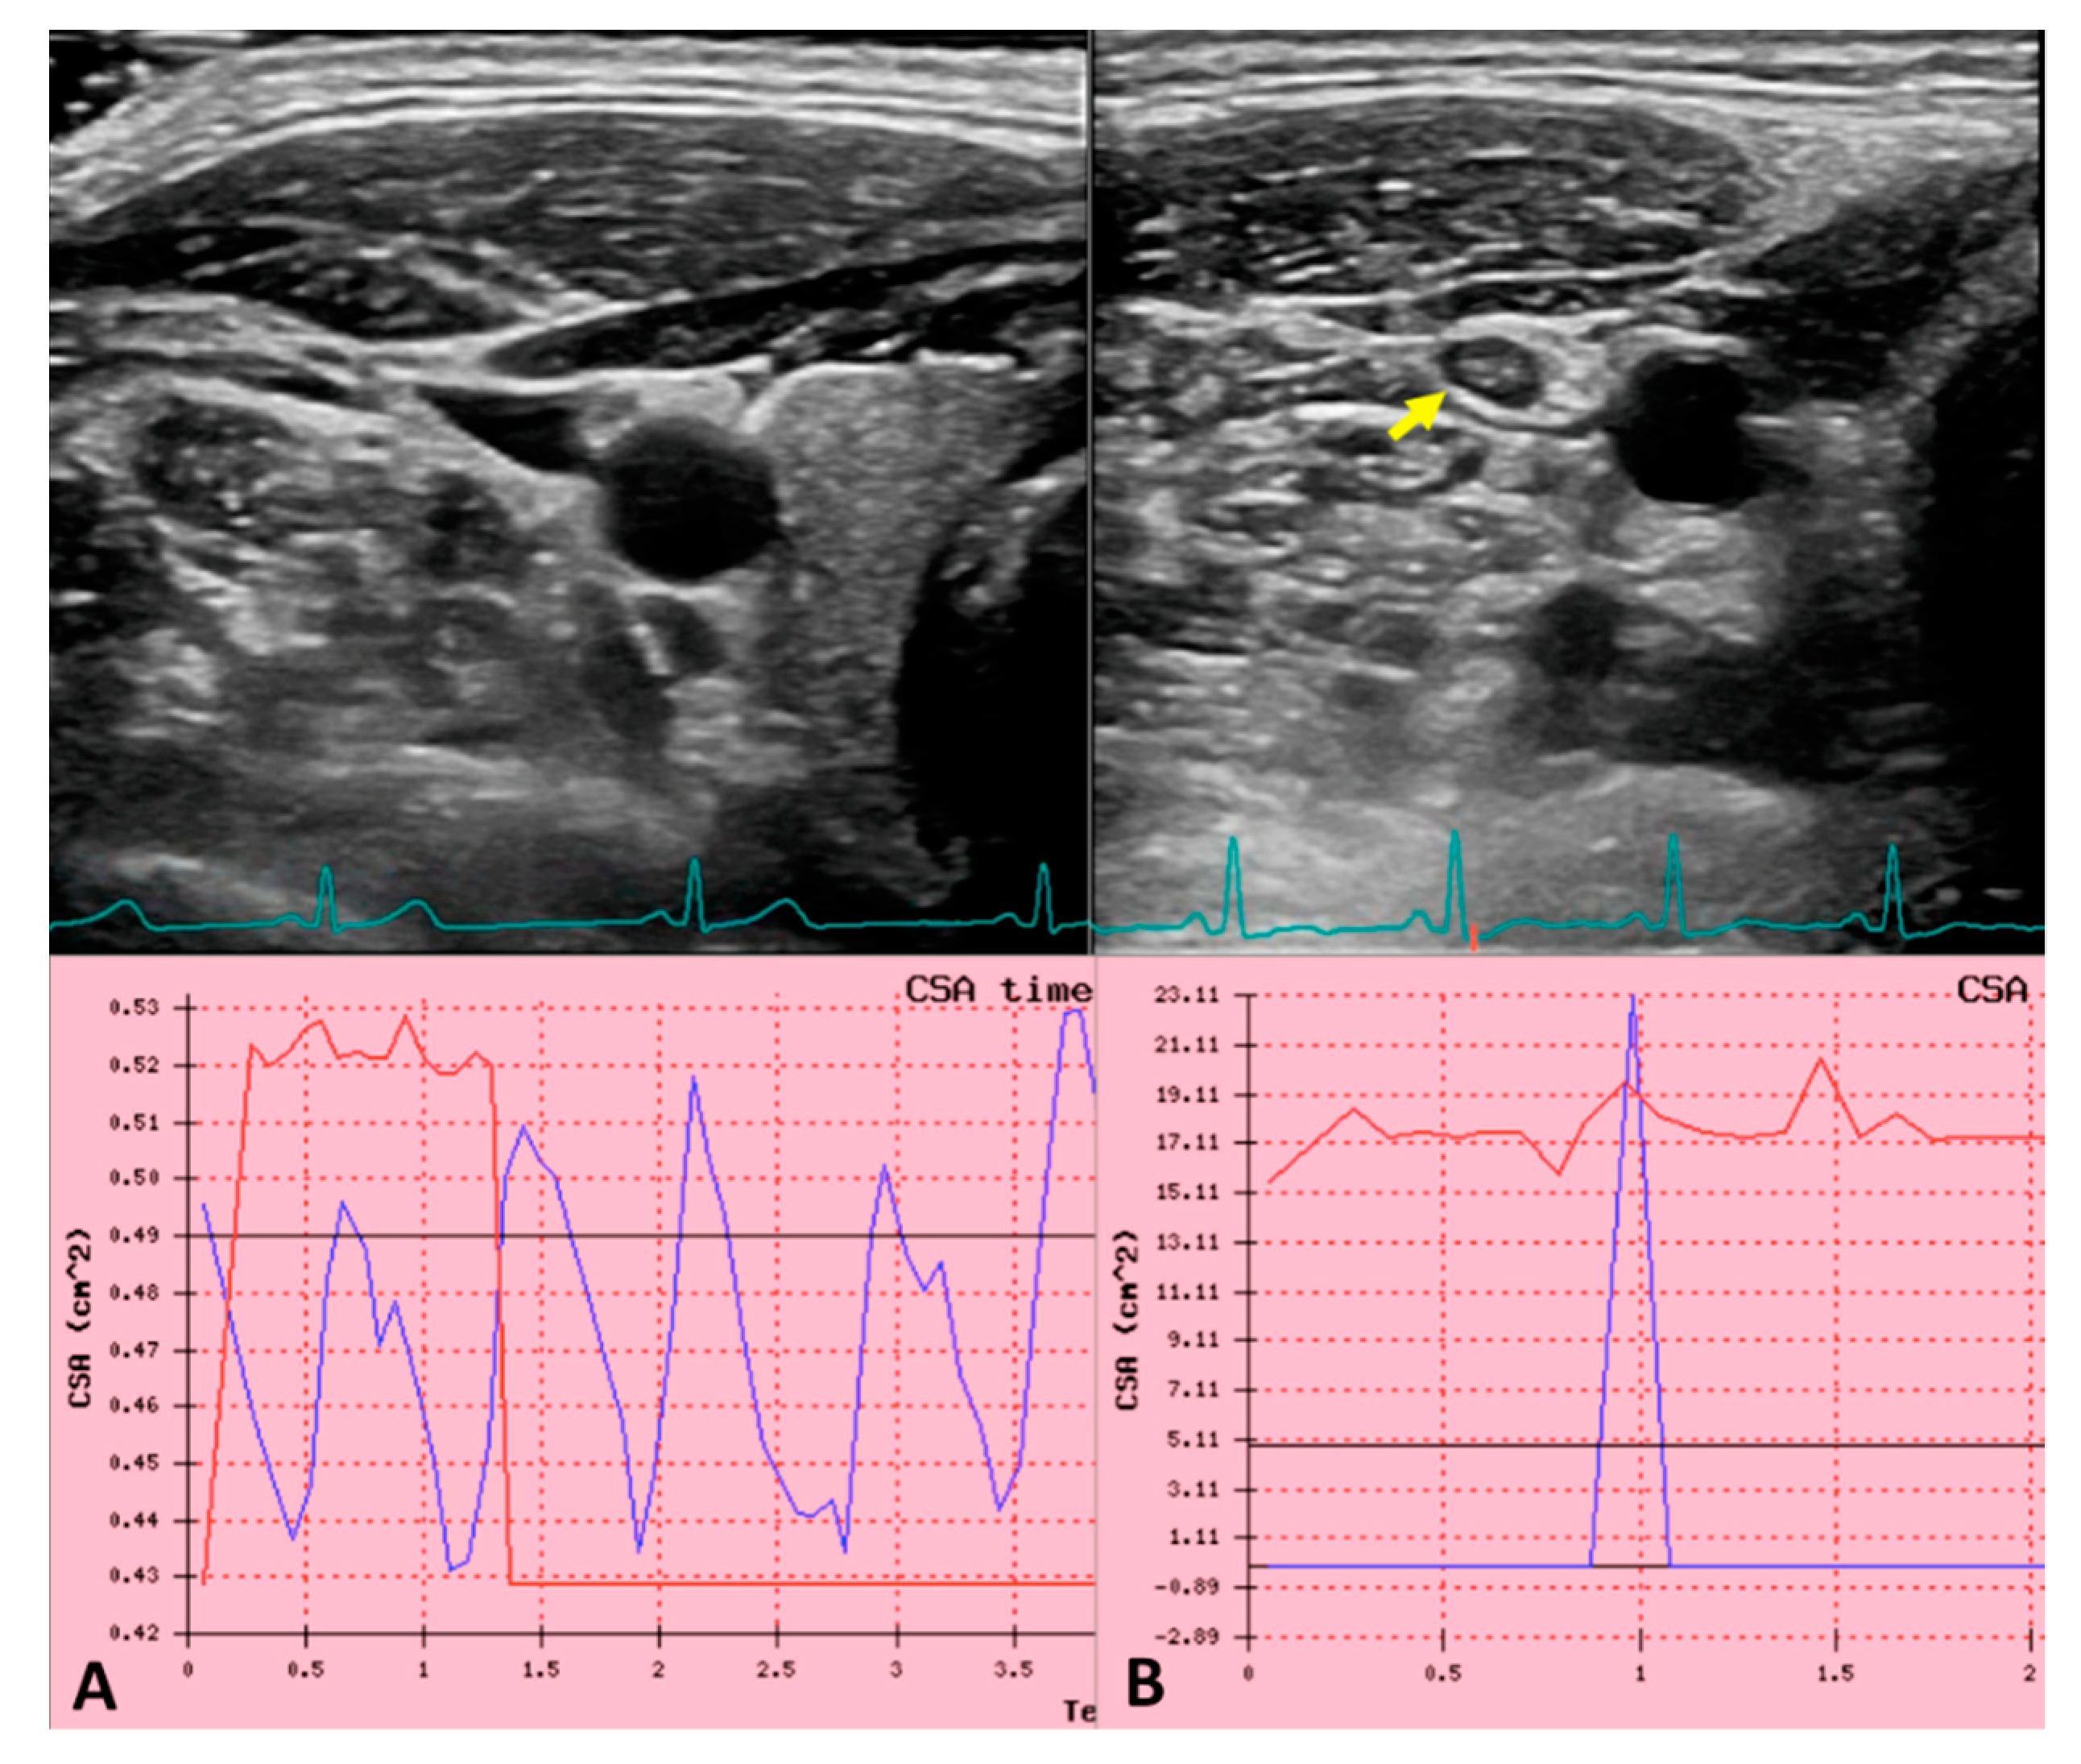

Ultrasound jugular venous pulse in normal and in internal jugular vein thrombosis (IJVthr) cases. (A) B-mode ultrasound (US) of the IJV and the common carotid artery at J2 level, in the transversal aspect of the neck. The green line corresponds to the ECG trace. The blue line in the diagram corresponds to the recorded JVP i.e., the sequence of cross-sectional area variation for cardiac beat. The red line corresponds to the synchronized ECG trace. (B) The yellow arrow shows an IJVthr. The disappearance of the sequential peaks of the ultrasound JVP is well apparent.

Flow in large vessels depends on the cardiac and respiratory cycles being not constant over time, particularly for a pulsatile vein such as the IJV, where cardiac pump transmits a sequence of well described waves along the entire vessel. This phenomenon is the ‘so called’ jugular venous pulse (JVP) and it is one of the main parameters of cardiac function. Indeed, it is also the reference physiological signal used to detect right atrial and central venous pressure (CVP) abnormalities in cardio-vascular diseases (CVDs) diagnosis [111]. Recently a novel technique has been described to evaluate the JVP by means of US, consisting of an accurate measurement of IJV CSA variation during cardiac cycle [115,122,123]. The protocol consisted in a IJV B-mode ultrasound videoclip recording, synchronized with 3-lead ECG, setting the frame rate at 30 frames/min in order to have the better time resolution. The assessment of the IJV CSA was performed using transverse plane at C5-C6 level [115,122].

The curve produced by the elaboration of CSA variation over the individual cardiac cycle, in case of physiological venous drainage, exactly corresponds to the JVP. Moreover, JVP trace permits a reliable and non-invasive estimation of central venous pressure. Using the lagging autocorrelation r-values as predictors, mean-CVP was predicted from ultrasound JVP with a mean-absolute-error of 1.45 cmH2O. Considering that JVP reflects right atrial pressure measurement, being directly connected to IJV without interruption [124] this curve could predict the presence of obstructions within the atrium-jugular segment. The presence of thrombus inside the IJV, subclavian vein, or superior vena cava would prevent the correct pressure wave propagation from the heart to the jugular, leading a change in the US-JVP curve. Further studies will be needed to demonstrate the changing in ultrasound JVP trace in course of IJVthr as shown in Figure 2.